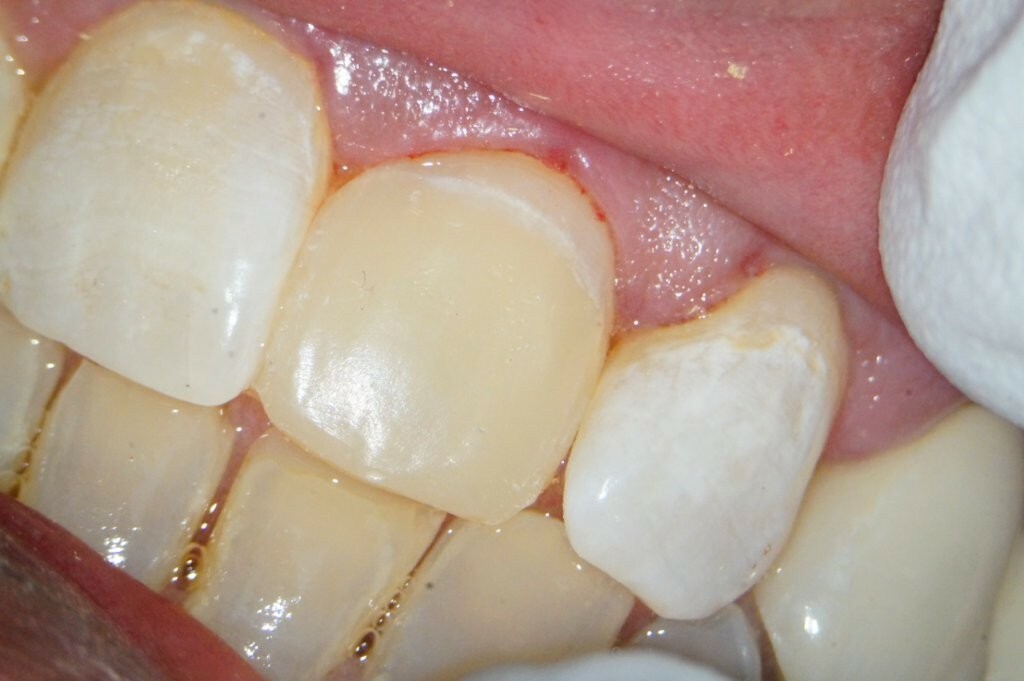

Der provisorische Aufbau erfolgte durch den Endodontologen mit vorab gefertigtem Silikonschlüssel mittels Tetric Flow und Ceram A3,5 als Abschluss der Single-Visit-Behandlung. Die endgültige Krone konnte am 12. Juni 2025 eingegliedert werden.

Die Vorteile der aufgezeigten Behandlungsstrategie liegen nicht nur in der Risikominimierung für den Patienten, sondern auch in der nahtlosen Verzahnung mit der prothetischen Versorgung: ein Termin weniger, keine erneute Anästhesie, kein Risiko einer bakteriellen Rekontamination. Somit eine interdisziplinäre Therapie, die funktionell, restaurativ und ästhetisch überzeugt. Der Patient konnte in weniger als zwei Monaten vollständig ästhetisch versorgt werden.